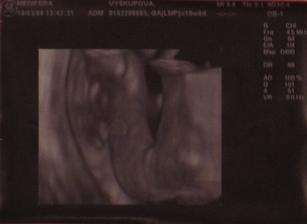

24.02.2009 boli sme na ďalšej tehu poradni. Chceli sme zistit ake bude pohlavie ale kedze sa stale trepotal a rozhadzoval rucickami a nozickami sa odtlacal 🙂 tak to neviem na 100% ale asi to doktor vidi na dievcatko. Takze sa tesime na našu malú cicušku🙂 Vážime už 180g takže pomaly priberáme. S našou asi cicuškou sme absolvovali aj našu svadbu. Zvladli sme to všetci traja úplne úžasne, veľmi dobre sme sa bavili až do rána do pol šiestej 🙂 Takže už spolu žijeme ako naozajsná rodinka 🙂